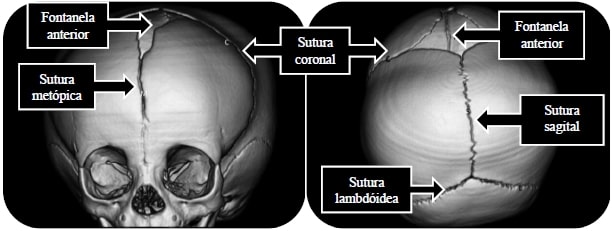

A cranioestenose coronal é uma anormalidade craniana que ocorre pela fusão antecipada de uma sutura craniana denominada sutura coronal. Ela é a segunda forma mais comum de cranioestenose. Quando uma sutura coronal é fusionada, chamamos de cranioestenose coronal unilateral (ou plagiocefalia anterior). Quando os dois lados são envolvidos, chamamos de cranioestenose bicoronal (ou braquicefalia). Para maiores informações acerca do crânio normal da criança, consultar: O crânio da criança.

A sutura coronal do recém-nascido é composta por tecido fibro-elástico, que é maleável e permite o crescimento do crânio à medida que o bebê se desenvolve e aumenta o seu volume cerebral. Cada sutura craniana (sagital, metópica, coronais, lambdóideas) possui um tempo estimado em que a sua fusão se completa. A sutura coronal demora para se fundir, completando sua fusão na segunda década de vida.

Em caso de alguma suspeita de anormalidade nas suturas ou fontanelas, a criança precisa ser avaliada por especialista, pois através da palpação da fontanela pode-se estimar se há algum indício de hipertensão intracraniana, pela análise do formato do crânio permite-se inferir se alguma sutura está fechada precocemente (cranioestenose) e através da presença de outros estigmas associados (como diferente posição das orelhas, formato assimétrico do posicionamento dos globos oculares, etc.) pode-se inferir a possibilidade de síndrome genética. A cranioestenose coronal pode estar associada à algumas síndromes, como Apert, Carpenter, Larsen, Roberts e com a alteração cromossômica trissomia do 21. Alguns exames de imagem são utilizados, como RX de crânio, tomografia de crânio com reconstrução 3D ou ressonância de crânio, nos quais se observa o comportamento das suturas e fontanelas.